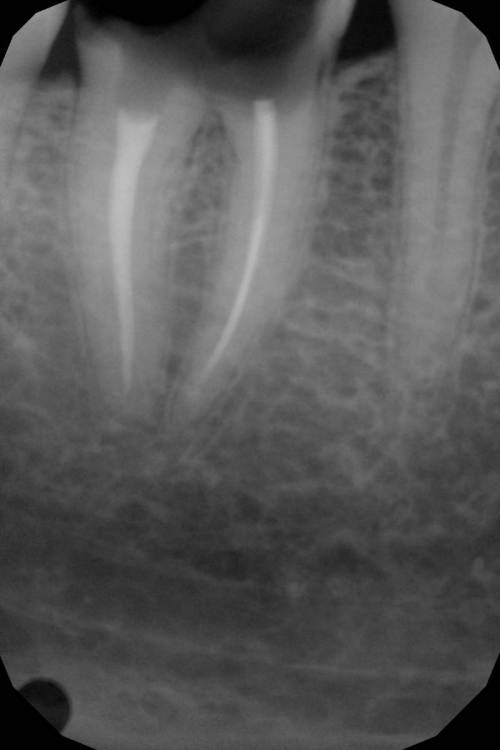

Алексей Петров Опубликовано 18 июня, 2021 Поделиться Опубликовано 18 июня, 2021 Добрый день! Получил от стоматолога рекомендацию на удаление зуба и установку импланта. Аргументация - осталось мало ткани зуба в зоне, соединяющей корни. Поэтому результаты лечения окажутся недолговечны: в случае установки коронки это место не выдержит нагрузки при жевании. Зуб - седьмой, снизу справа. Уважаемые специалисты, прошу вас прокомментировать корректность рекомендации к удалению. Ссылка на комментарий

АнтонТЛТ Опубликовано 18 июня, 2021 Поделиться Опубликовано 18 июня, 2021 Рекомендации корректны 2 1 1 Ссылка на комментарий